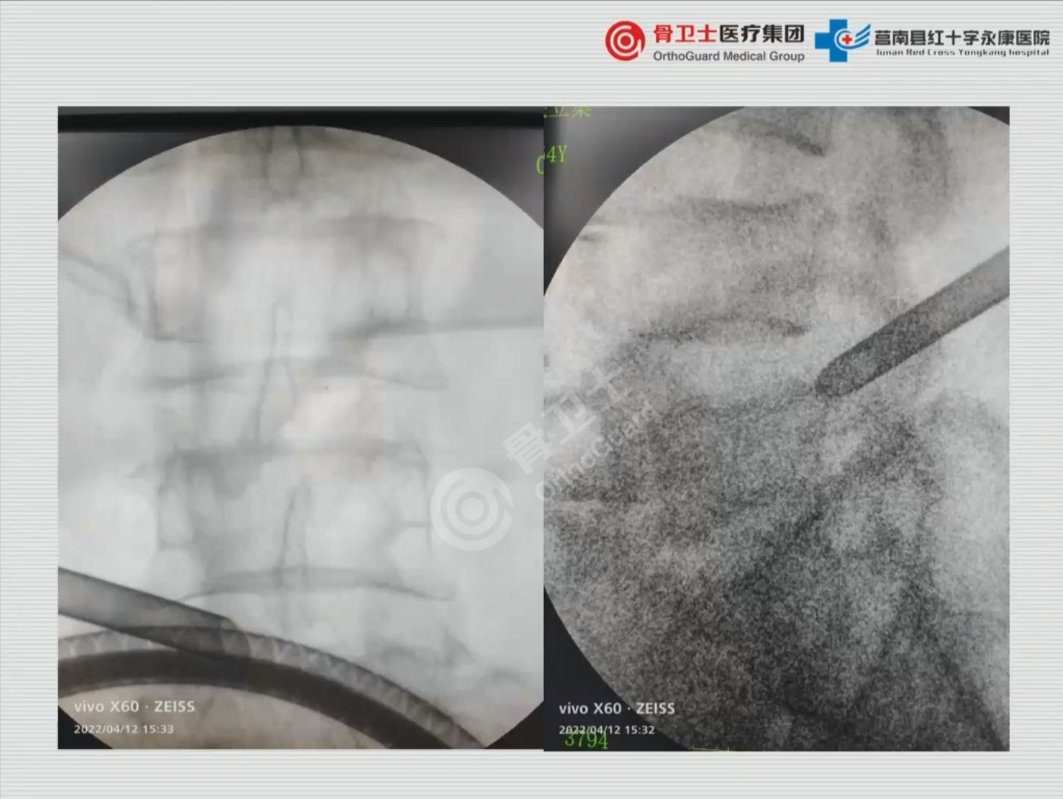

▲为患者进行椎间孔镜手术,术中可见神经根周围松解完全,神经根滑动良好

对于该患者治疗方案的选择,吴闻文教授表示,椎间孔镜治疗是最适合该患者的方式。术式的选择,要根据神经根判断,如果患者表现在孔狭窄,孔镜减压最直接,相对创伤最小;如果腰4/5节段需要重点减压的是出口根,或者孔这个地方,或者是上关节突的尖端,则选择孔镜;如果突出位置比较偏内,偏中线,主要减压的是走行根,则选择UBE手术,减压比较充分,最大限度让患者受益。